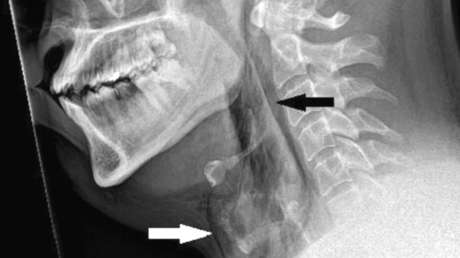

La historia, documentada este mes en la revista médica BMJ Case Reports, señala que el paciente, de unos 30 años, comenzó a sufrir un intenso dolor en el cuello inmediatamente después querer evitar un fuerte estornudo tapándose la nariz y manteniendo la boca cerrada al mismo tiempo, mientras conducía. Rápidamente acudió a urgencias del hospital Ninewells de la ciudad de Dundee, donde fue sometido a una radiografía y tomografía de cuello y tórax, que revelaron un pequeño "desgarro traqueal" a nivel de la tercera y cuarta vértebra torácica.